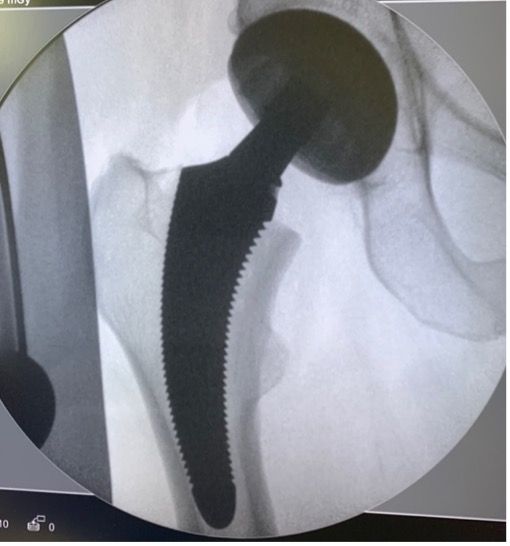

Planning - The intervention begins before the incision, with the preparation. As Franklin said “If you fail to plan, you are planning to fail”. Pre-operative planning is an integral part of the success of the operation, in that it involves assessing the native hip parameters (which should be restored) and anticipating any peri-operative difficulties. This planning means that the precise size of the final stem can be determined, ensuring optimal intramedullary filling, and the correct height of the femoral neck cut can be identified. Under-sizing risks secondary subsidence, especially in somewhat valgus tilted femurs . Stem positioning must follow the calcar rather than the diaphyseal axis, which will enable the femoral offset to be restored. Restoring an optimal overall offset also depends on the depth to which the socket is burred, as this may sometimes need to be compensated for on the femoral side. Finally, it is important to take femoral torsion into account. All this points to the value of 3-dimensional planning systems that take these parameters into account (EOS or CT scan), and are more complete than the conventional practice of sketching on AP radiographs.

Metaphyseal preparation - This starts by opening the femoral shaft using a specific curved rasp, which will guide the passage of the compactors of gradually increasing sizes. This preparation must be done as close as possible to the calcar. If the bone is very dense, a curette may be needed to prepare the calcar if the intention is to position a stem in a varus tilt or for the greater trochanter if a valgus position is the objective. This preparation should not be excessive since the principle of this implant is to compact the metaphyseal bone rather than to remove it. This step should preferably not be carried out before inserting the last compactor due to the risk of destabilising the final implant. If the surgeon is unsure, fluoroscopic guidance may be useful to confirm the positioning of the final compactor and to ensure that the plan has been followed and filling is correct. In any case this is what Loweg recommends. out cas ce que conseille Loweg [19].